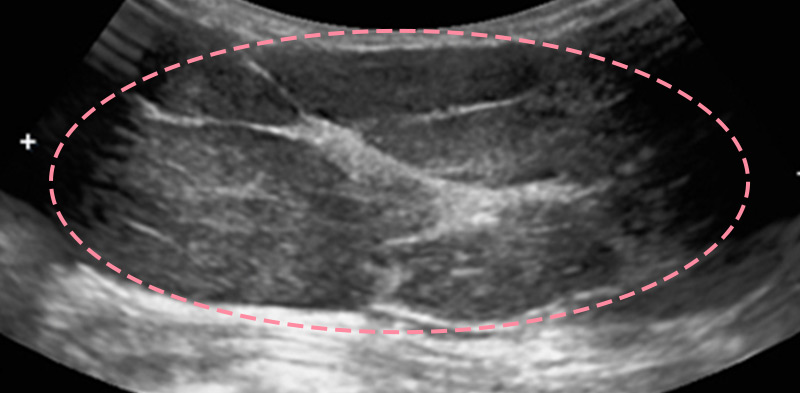

유방 양성 종양은 한 개만 나타나는 것이 아니라 동시다발적으로 생겨나기도 합니다.

여러 개의 양성 종양 제거는 정상적인 유방 조직을 온전히 보전할 수 있도록 섬세한 시술이 필요합니다.

한송이 원장은 다발성 종양 제거에 대한 풍부한 경험을 토대로, 무리 없이 맘모톰 조직검사 및 제거를 진행했습니다.

맘모톰시술 6개월 후 유방초음파 검사 시행 결과 종양이 깨끗하게 제거됨을 확인했으며, 약간의 반흔 조직이 남았으나 시간이 지나면서 대부분 사라지기 때문에 좋은 예후가 기대되었습니다.